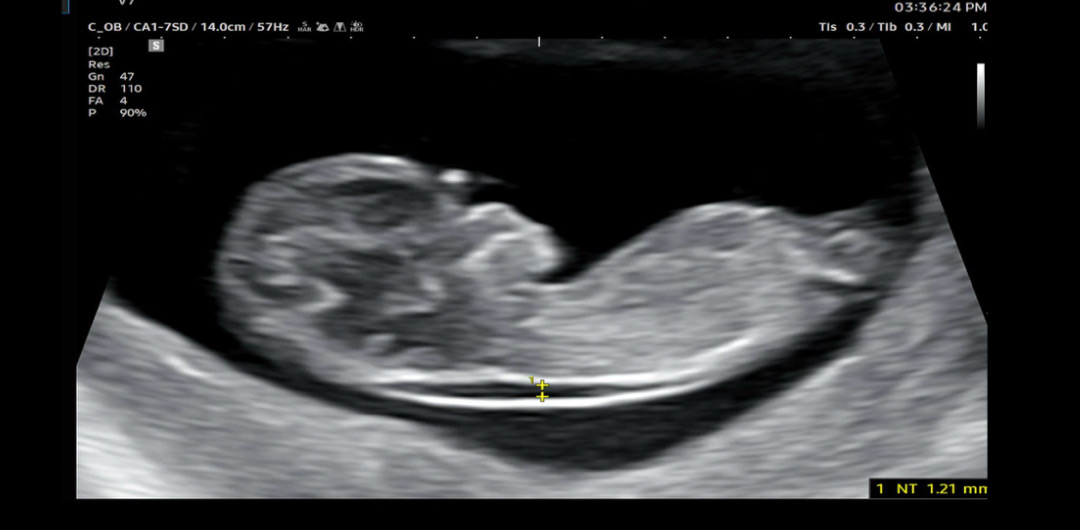

11주5일차 성별

안녕하세요! 한달만에 아기 보러 다녀왔는데 성별 힌트를 핑크로 살짝 주시더라구요. 각도법 보실 줄 아시는 분들 한번 봐주실 수 있을까요~?

딸같아요! 매끄럽네요